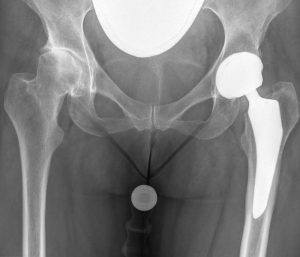

In unserer Praxis führt Dr. Sebastian Köller voll- oder teilendoprothetische Ersatzoperationen an Hüften und Knien durch. Er verfügt über eine langjährige fachliche Expertise mit ca. 1.700 Implantationen. Als Oberarzt und Hauptoperateur des Endoprothese Zentrum der Maximalversorgung werden die Eingriffe im Ortenau Klinikum in Kehl durchgeführt. Ein breites Spektrum an Prothesentypen und Materialien gewährt eine individuelle, ideale Versorgung.

Sowohl für Knie als auch Hüften stehen unterschiedliche Implantate und Kombinationen zur Verfügung. Die Entscheidung, welches für Sie am ehesten geeignet ist, kann bereits vor der Operation gut abgeschätzt werden.

Eine Rolle spielt hier neben dem Patientenalter, dem Ausmaß der Arthrose sowie dem Aktivitätsgrad auch eine computerunterstützte Planung anhand eines digitalen Röntgenbildes. Letztendlich kann aber auch während der Operation grundsätzlich auf andere Systeme gewechselt werden, falls dies der Operateur für erforderlich erachtet.

Für den Ersatz des Hüftgelenkes werden sowohl moderne Standardprothesen wie auch so genannte Kurzschaftprothesen verwendet. Letztere werden überwiegend bei jüngeren Patienten mit noch ausreichend guter Knochensubstanz eingesetzt. Die Verankerung im Knochen kann sowohl zementfrei (am häufigsten), teilweise zementiert (sog. Hybridprothese) oder voll zementiert erfolgen. Alle Varianten haben Vor- und Nachteile. Hinsichtlich der Haltbarkeit gibt es jedoch keine wesentlichen Unterschiede.